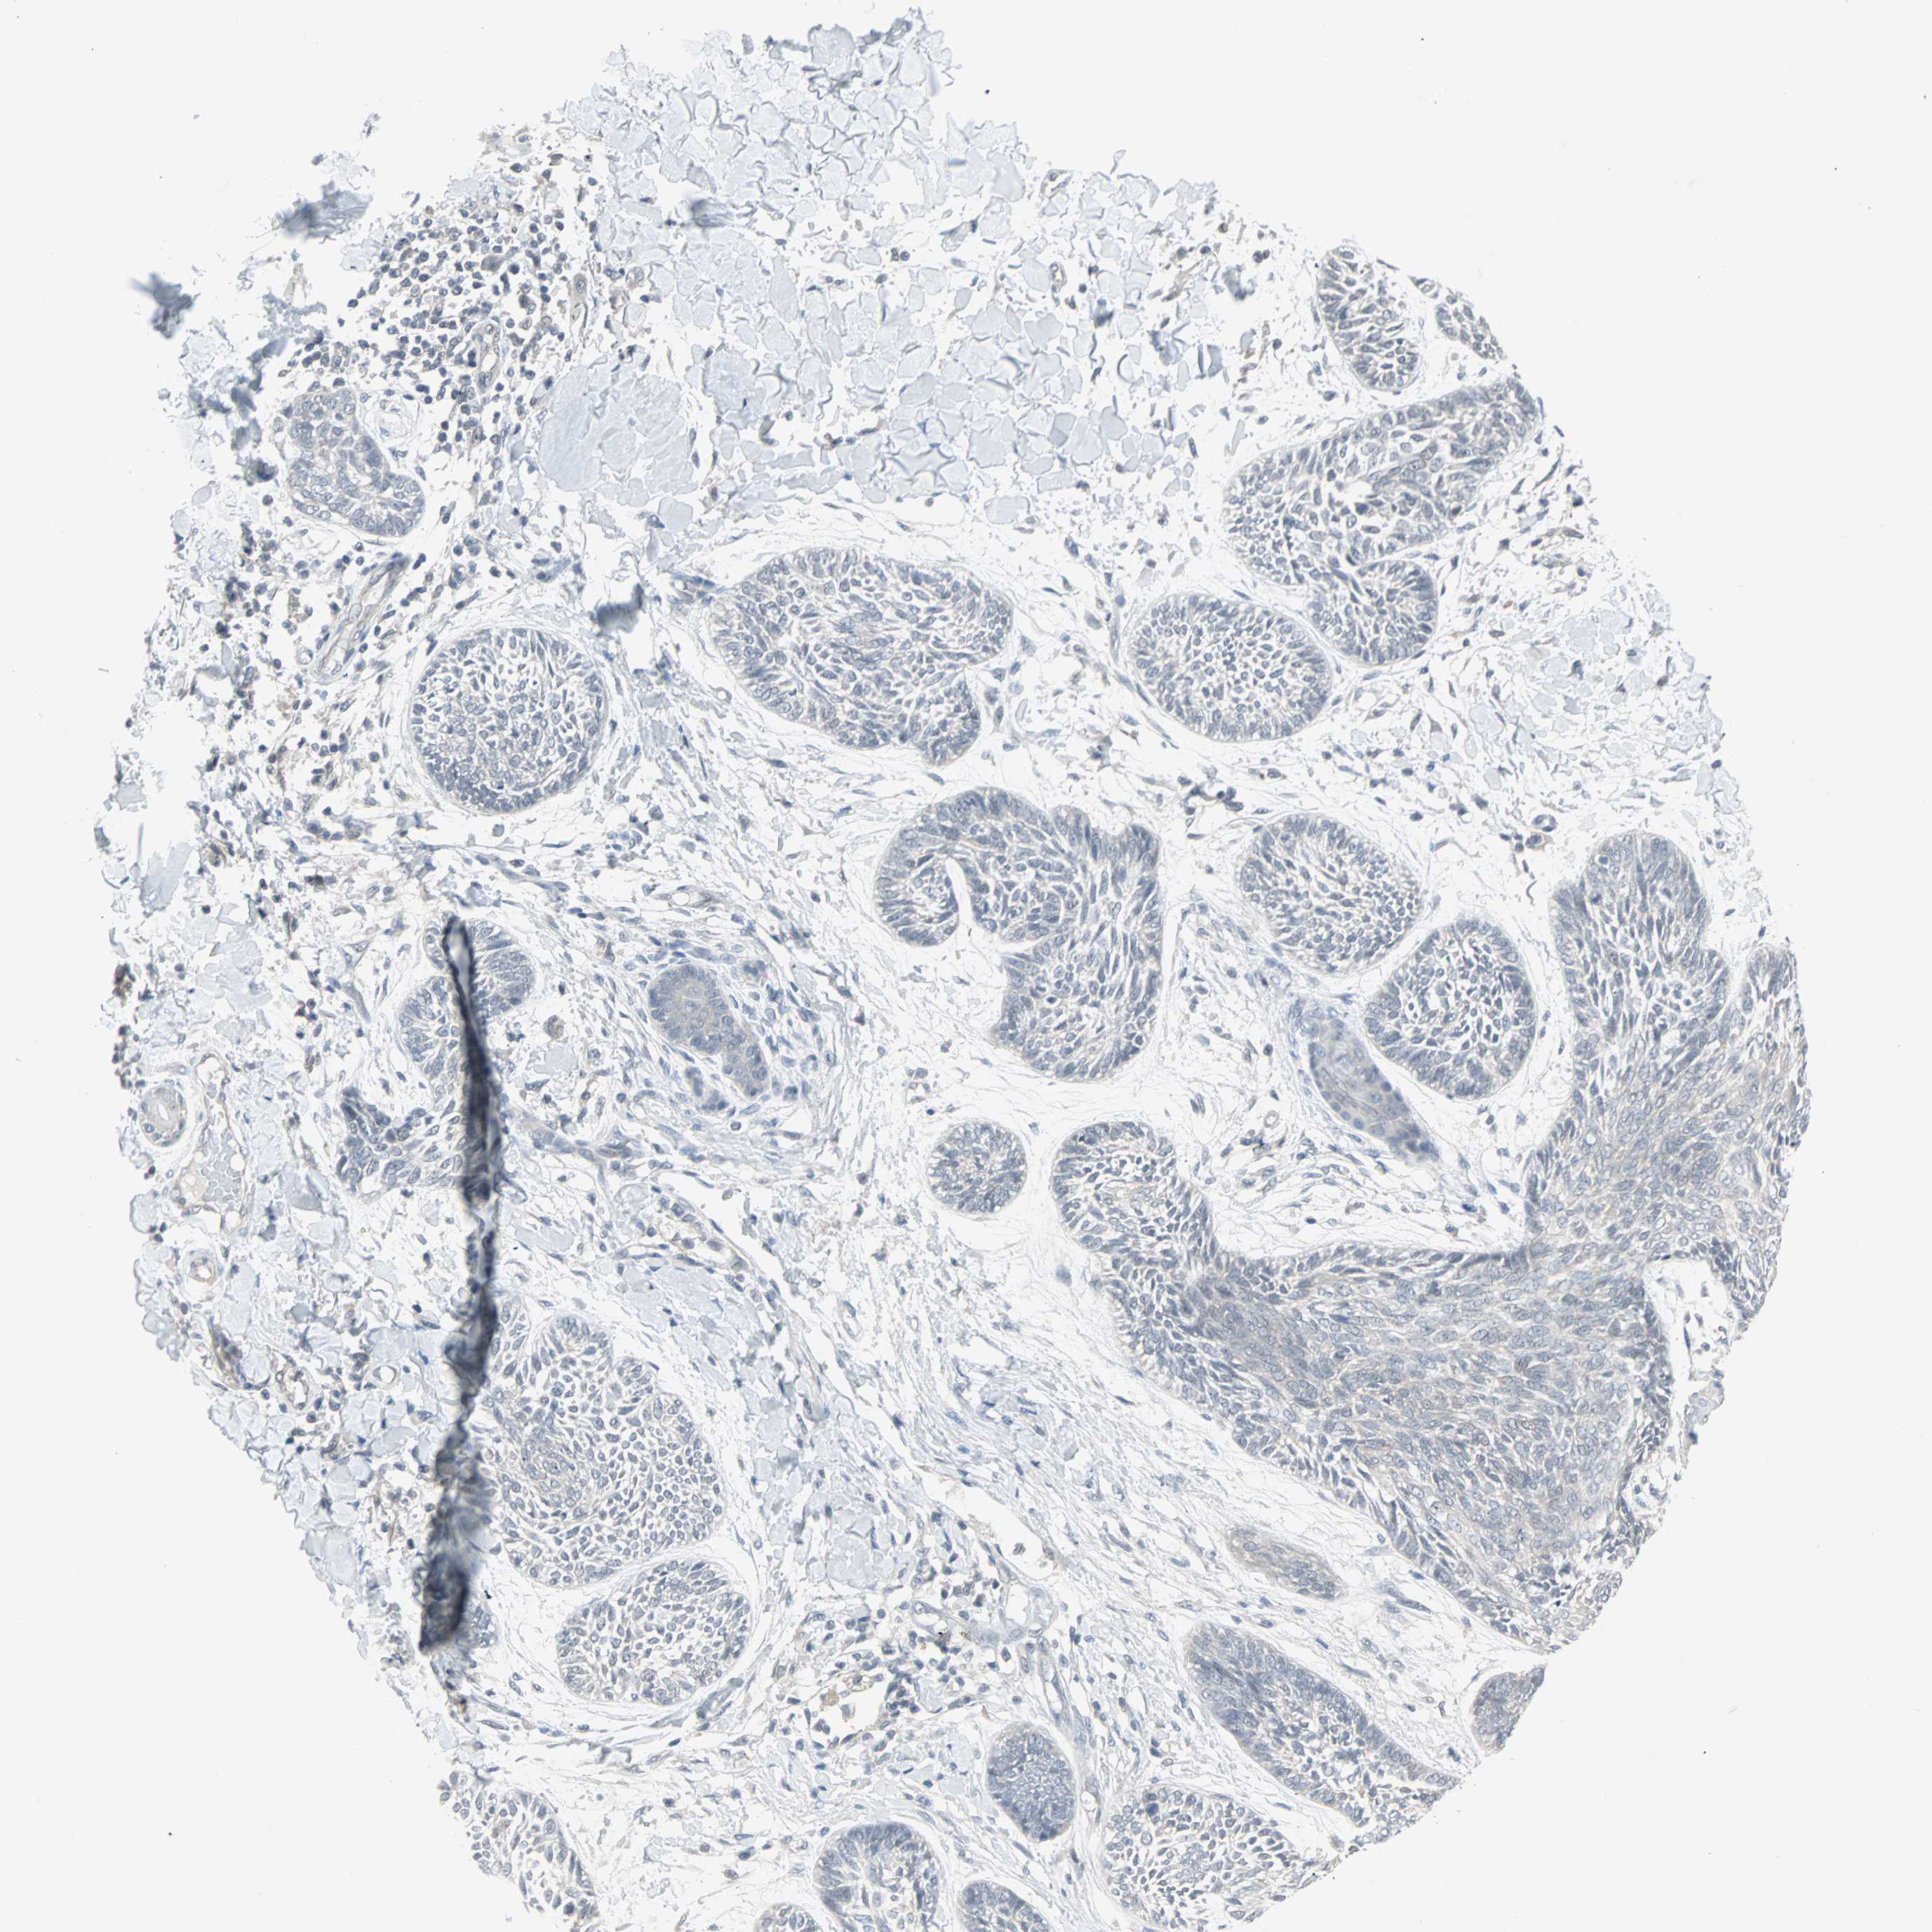

SKIN CANCER - Protein expressioni

A mouse-over function shows sample information and annotation data. Click on an image to view it in a full screen mode. Samples can be filtered based on level of antibody staining by selecting one or several of the following categories: high, medium, low and not detected. The assay and annotation is described here.

Antibody stainingi

Antibody staining in the annotated cell types in the current human tissue is reported as not detected, low, medium, or high, based on conventional immunohistochemistry profiling in selected tissues. This score is based on the combination of the staining intensity and fraction of stained cells.

Each image is clickable and will lead to virtual microscopy that enables deeper exploration of all samples and also displays staining intensity scores, fraction scores and subcellular localization as well as patient and tissue information for each sample.

CAB022068

Staining

High

Medium

Low

Not detected

Intensity

Strong

Moderate

Weak

Negative

Quantity

>75%

75%-25%

<25%

None

Location

Nuclear

Cytoplasmic/membranous

Cytoplasmic/membranous,nuclear

Squamous cell carcinoma, NOS